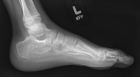

7 year old male who has had a six month history of left heel pain which was first noted with difficulty putting on his socks.

PMX- neurofibromatosis & scoliosis. Left foot pain is sharp, severe at times, constant in nature, worse with activity. Family describes the discomfort as worsening. It is made better with rest. He has no other history of trauma.